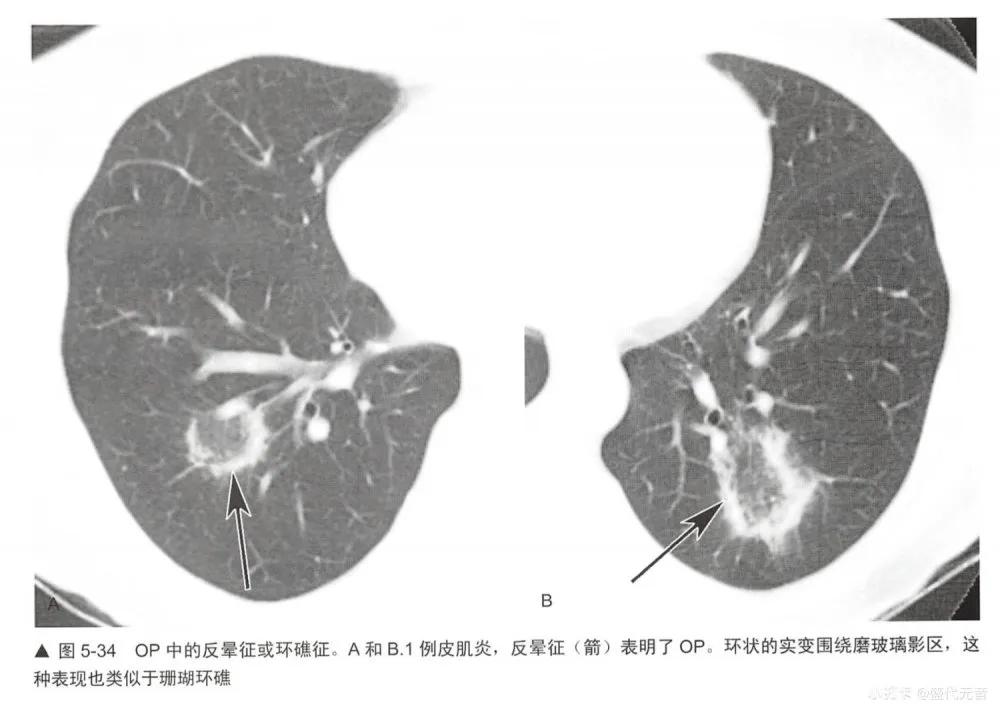

■实变和“反晕征”或“环礁征”

局灶区实变或磨玻璃影可出现所谓的“反晕征”或“环礁征”,这时磨玻璃影被致密的环或新月形实变包绕(与珊瑚环礁相似,或“晕征”的反义词)(图4-47,图5-34,图5-35)。 这种表现高度提示0P,在两篇不同的研究中其发生率为12%和19%。它也常见于慢性嗜酸性肺炎,后者非常像0P。反晕征或环礁征也见于其他疾病的报道,如Wegener肉芽肿(多血管炎性肉芽肿);各种感染,尤其是副球孢子菌病,毛霉菌病,曲霉菌病,细菌性感染和结核;结节病; 肿瘤;淋巴瘤样肉芽肿病和梗死。值得注意的是,这些疾病都可能合并组织学上的0P。在几篇这种少见表现的报道中,磨玻璃影主要符合肺泡间隔炎症,而致密的实变区代表肺泡内炎性浸润。

虽然该征提示0P,但也可见于多种感染性和非感染性疾病。因此,该征象的存在并不能直接排除其他可能的诊断。深入分析HRCT的其他征象有助于鉴别诊断,为了最终确定原因常需组织学评估。